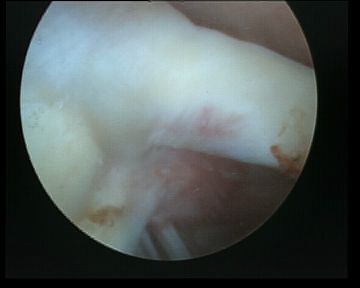

| Inferior glenohumeral ligament (IGHL) | |

|---|---|

|

Origin: Inferior 2/3 glenoid and labrum Insertion: Anatomical neck humerus

Anterior band: antero-inferior glenoid to 3 o'clock Posterior band: postero-inferior glenoid to 9 o'clock Axillary pouch between two bands |

| Most important ligament in terms of stability | Stabilizes arm at 90 degrees of abduction |

Anterior IGHL glenoid attachment |

IGHL humeral attachment |

Inferior recess

Loose body in inferior recess

Undersurface supraspinatus - abduct arm

Infraspinatus / bare area / Hill Sachs